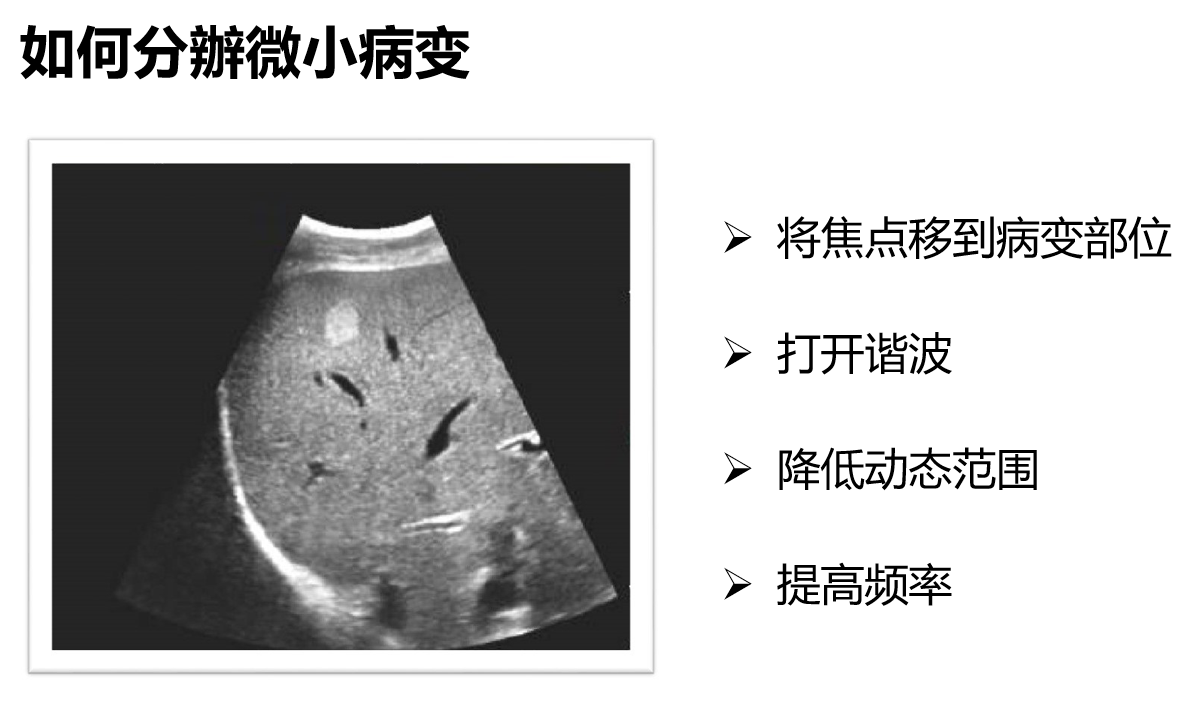

如何分辨微小的病变?像这个图上的血管瘤。

可以将焦点移到病变部位;打开谐波;降低动态范围;提高频率等等都可以提高分辨率。